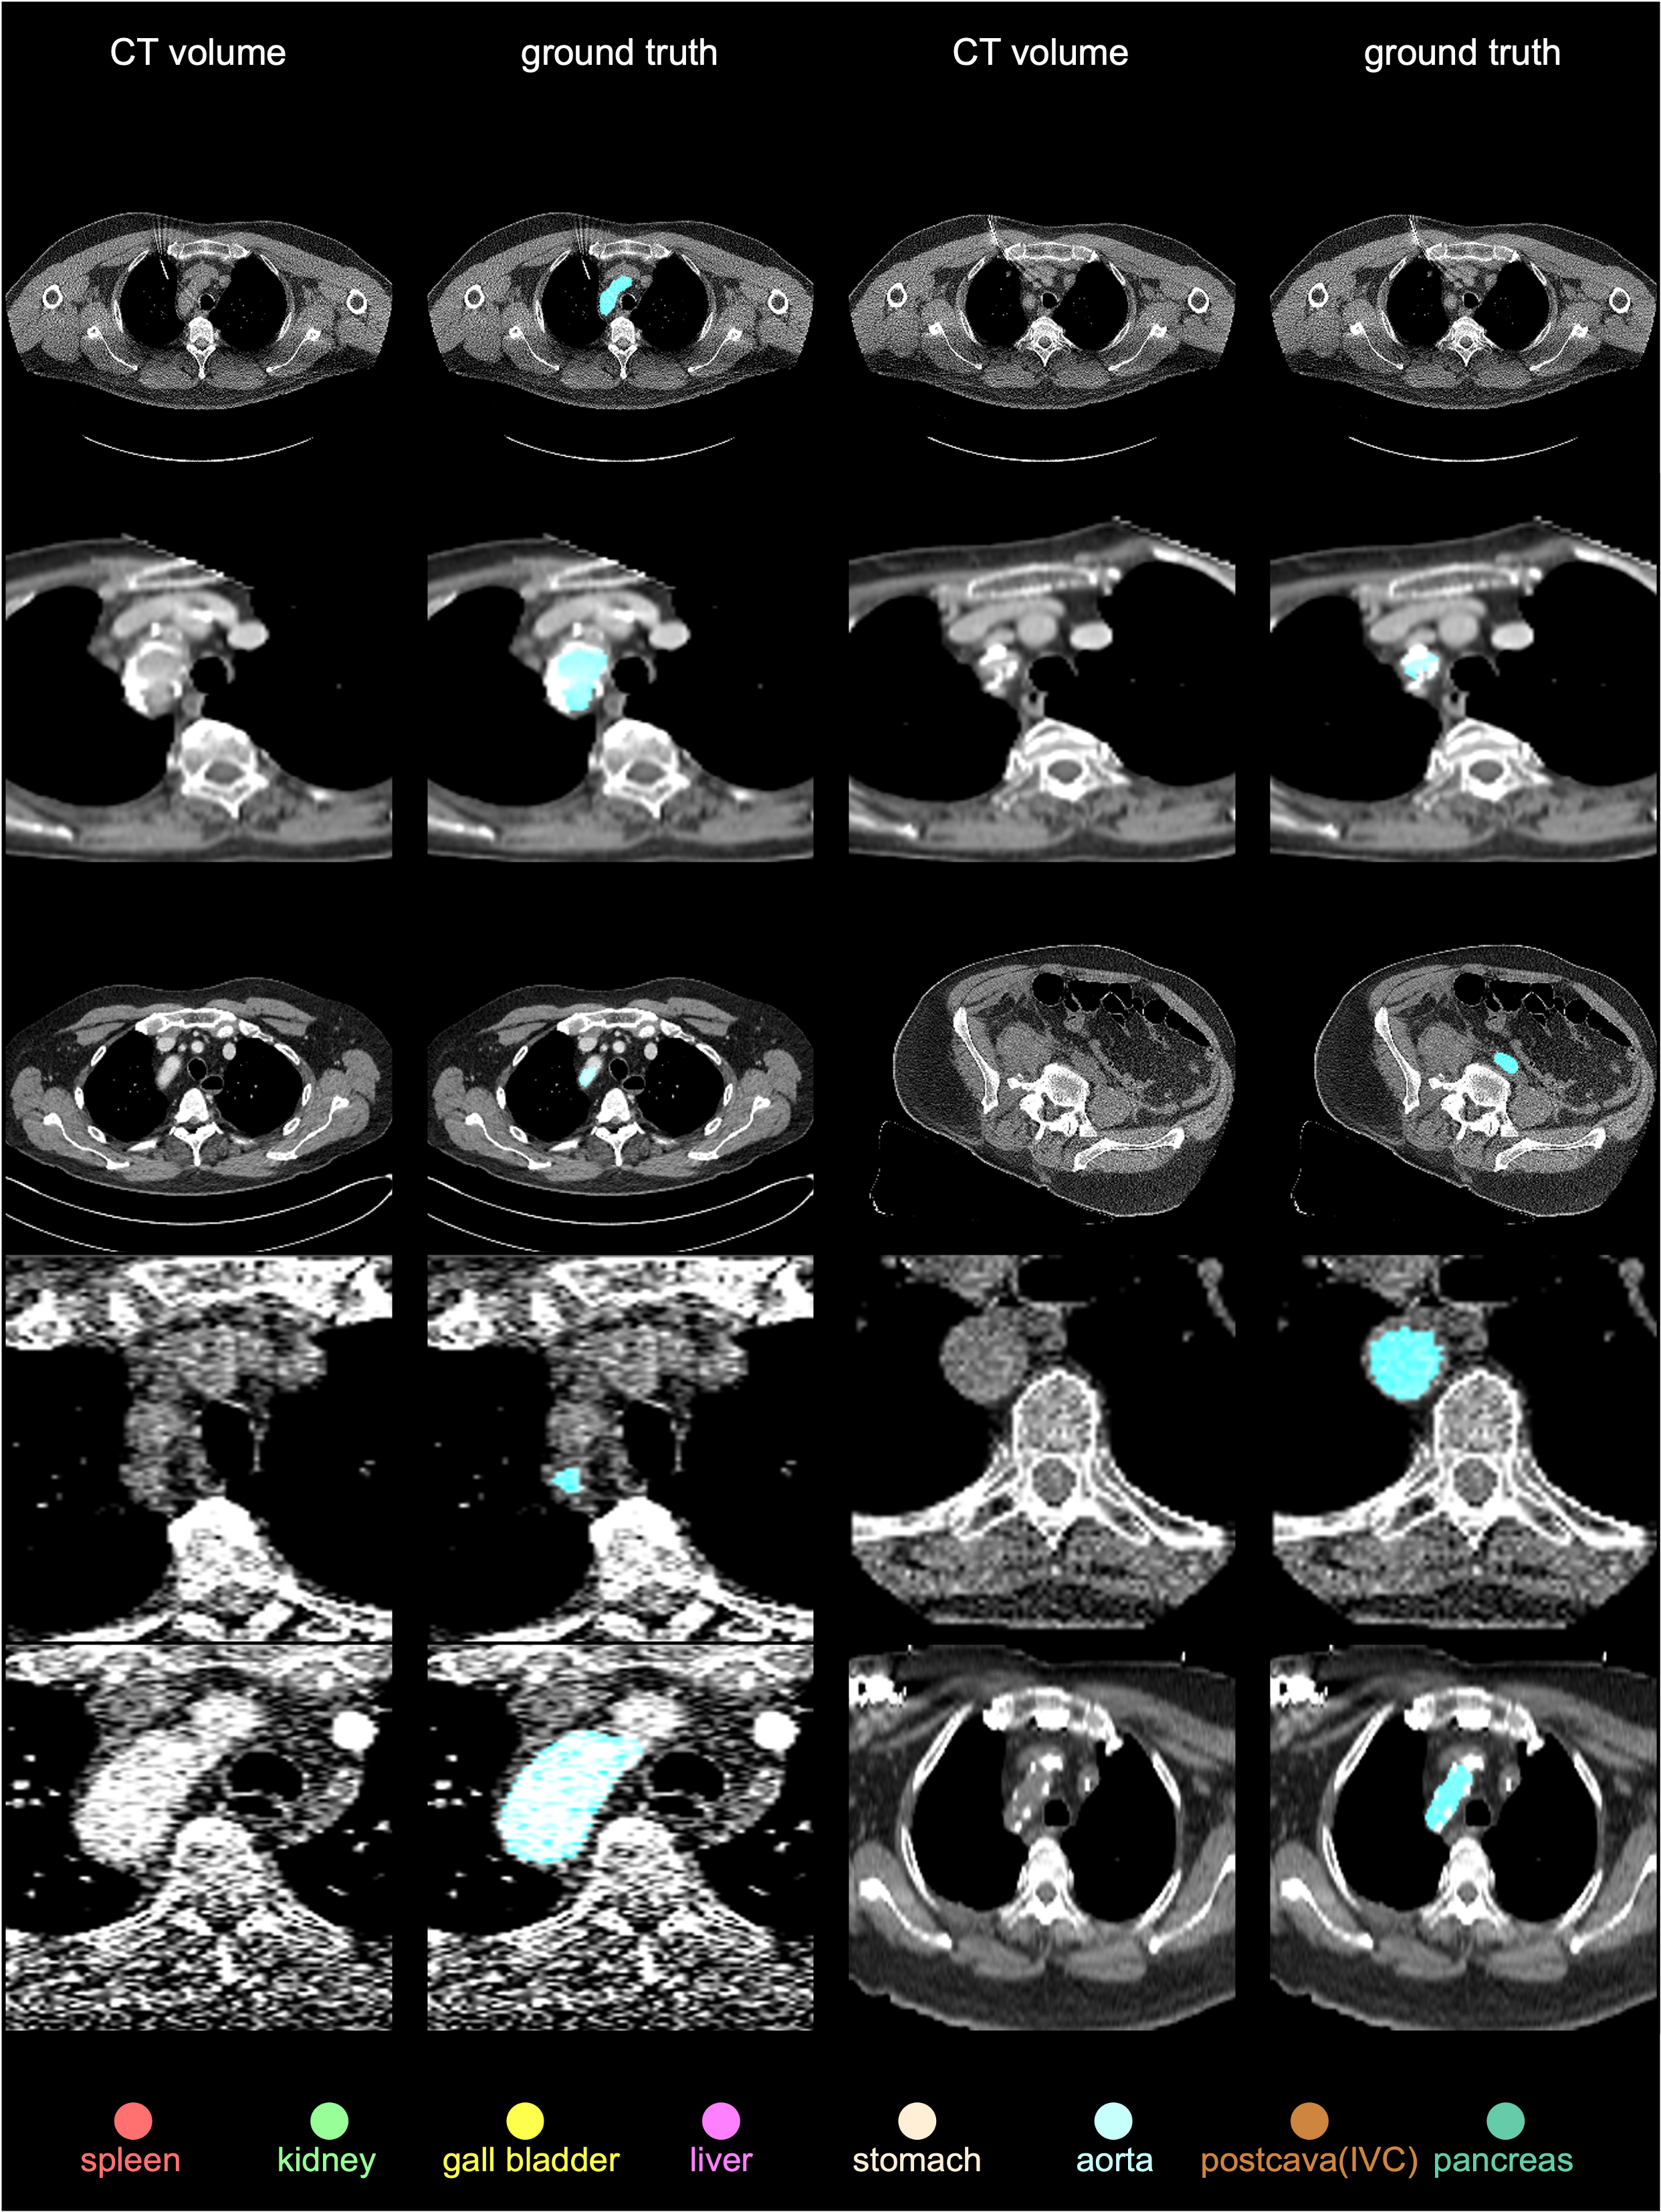

We used one training dataset and two test datasets to perform a comprehensive out-of-distribution benchmark. The training and test datasets were collected from many hospitals worldwide. Figure 1 shows the demographics of the two test datasets, JHH and TotalSegmentator; Appendix Figures 34 provide examples of CT scans and per-voxel annotations for various demographic groups across all datasets. The JHH dataset is proprietary and used for third-party evaluation; participants do not have access to the CT scans or their annotations. TotalSegmentator is a publicly available dataset; we did not inform the inventors beforehand of its use in our evaluation and confirmed that their AI algorithms had not been trained on this dataset. We included this public dataset to enable future participants to easily compare their algorithms with our benchmark.

TotalSegmentatorV2N𝑁Nitalic_N=743; publicly available for out-of-distribution test purposes—is from 10 institutes within the University Hospital Basel (Switzerland) picture archiving and communication system (PACS) [wasserthal2022totalsegmentator]. Being one of the largest public CT datasets, TotalSegmentator, under Apache License 2.0, was annotated by AI-assisted radiologists. It comprises both contrast-enhanced and non-contrast images, with per-sample metadata including age, sex, scanner details, diagnosis, and institution. We report AI performance on a subset of TotalSegmentator dataset222TotalSegmentator offers 1,228 CT scans, but 485 scans were included into FLARE and subsequently inherited by AbdomenAtlas 1.0. As a result, we used only the remaining 743 scans for evaluation. Unlike JHH, this evaluation set does not come from completely unseen hospitals. However, there is a significant distribution shift between the TotalSegmentator data within AbdomenAtlas and the data in our test set (see Appendix A.2). in Table 3 and its official test set in Appendix Tables 1112.